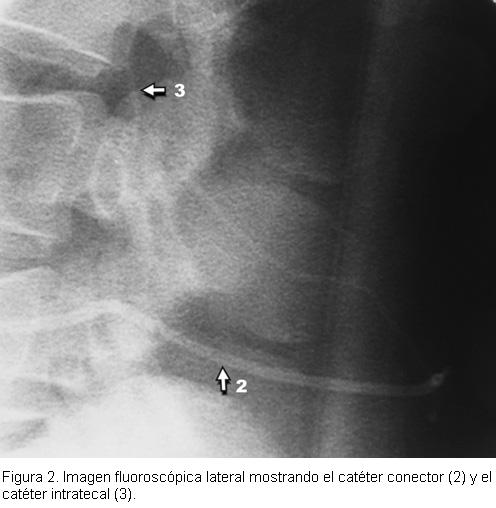

Se colocó la bomba a nivel subcutáneo en un bolsillo supra-aponeurótico paraumbilical derecho (figura 1), y mediante una tunelización bajo la piel se pasó el catéter conector que se unió al extremo distal del catéter intratecal (figura 2). Se llenó la bomba con 3 ml (30 mg) de sulfato de morfina al 1% sin conservantes y 57 ml. de suero fisiológico, se realizó la fijación del implante y se cerró la piel por planos.